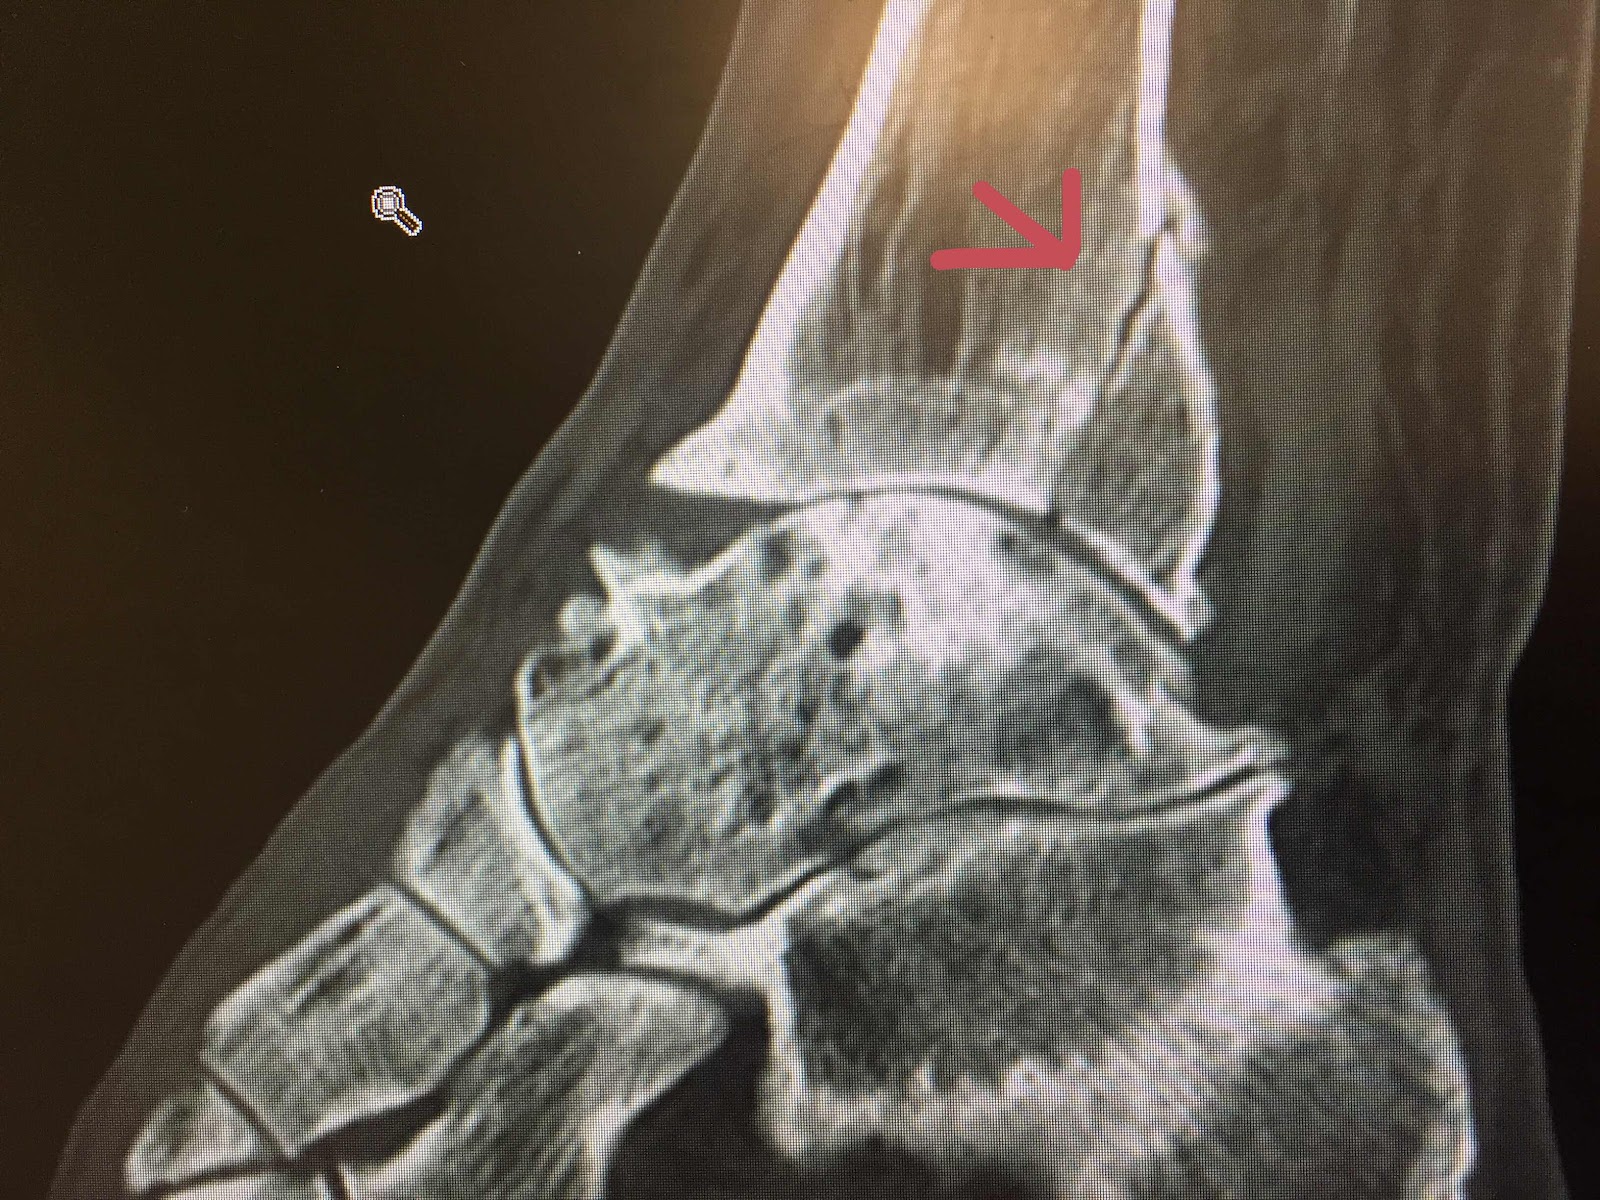

For the last 6 weeks he has been in excruciating pain and swelling around his ankle. We thought he had damaged his already broken and repaired ankle. He’s had an X-ray, CT Scan and Ultrasound. He saw a specialist today who told him that there was no more damage to his ankle but has been walking around for the last 6 weeks with a broken Fibula!

It’s now too late to have any surgery on it as it’s started to repair.   The pain is now starting to reduce a little and hopefully he’ll keep seeing some improvement as it mends. Can take up to 2 years to repair fully.